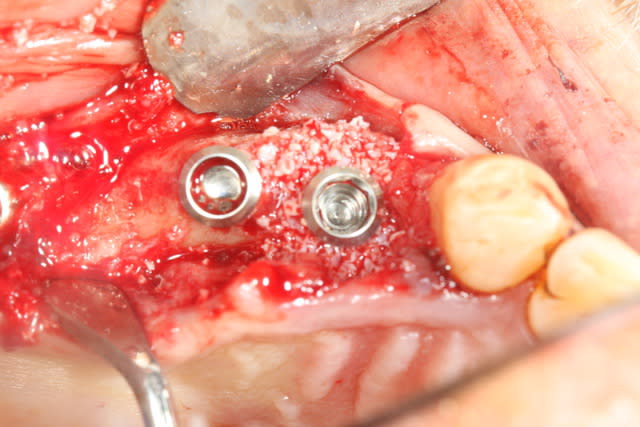

voici mon premier cas d'Extraction implantation Immediate...

1/as tu place une membrane pour ta rog?

2/ pourquoi le faire en un temps? Le risque d'echec de la rog est majore dans cette approche je pense?

Justement cartman...

J'avais prévu en amont; bio oss et membrane.

En examinant la paroi vestibulaire de l’alvéole après extraction...j'ai pensé que la résorption faisant l'option implantaire serait plus compliquée par la suite. J'ai donc posé l'implant en 24;

A posteriori je me dit que j'aurai du poser la membrane autour de l'implant pour éviter la compétition cellulaire et optimiser mon comblement.

On va dire que j'ai été ptit bras sur ce coup.

bravo ! Pour la 24, la prochaine fois commence avec un trépan dans le septum:

tes forets suivant ne seront plus déviés et tu aura un peu d'os à mélanger au Bio-Oss

Ici, pas besoins de membrane car ton défaut osseux est à 4 parois

dommage que tu sois si timide pour la longueur des implants, y'avait de quoi mettre un peu plus long et faire une mise en esthétique immédiate

oui t'as raison, mais comme je ne suis encore rompu au bon positionnement tridimensionnel des implants, j'ai préféré me laisser un peu de marge au cas ou je dévie...